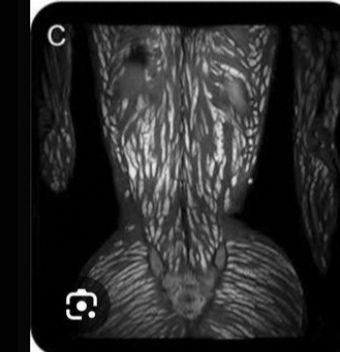

Les extractions de maggot ou d'abcès géants ya que moi qui aime ici ?

C'est trop satisfaisant un drain d'abcés